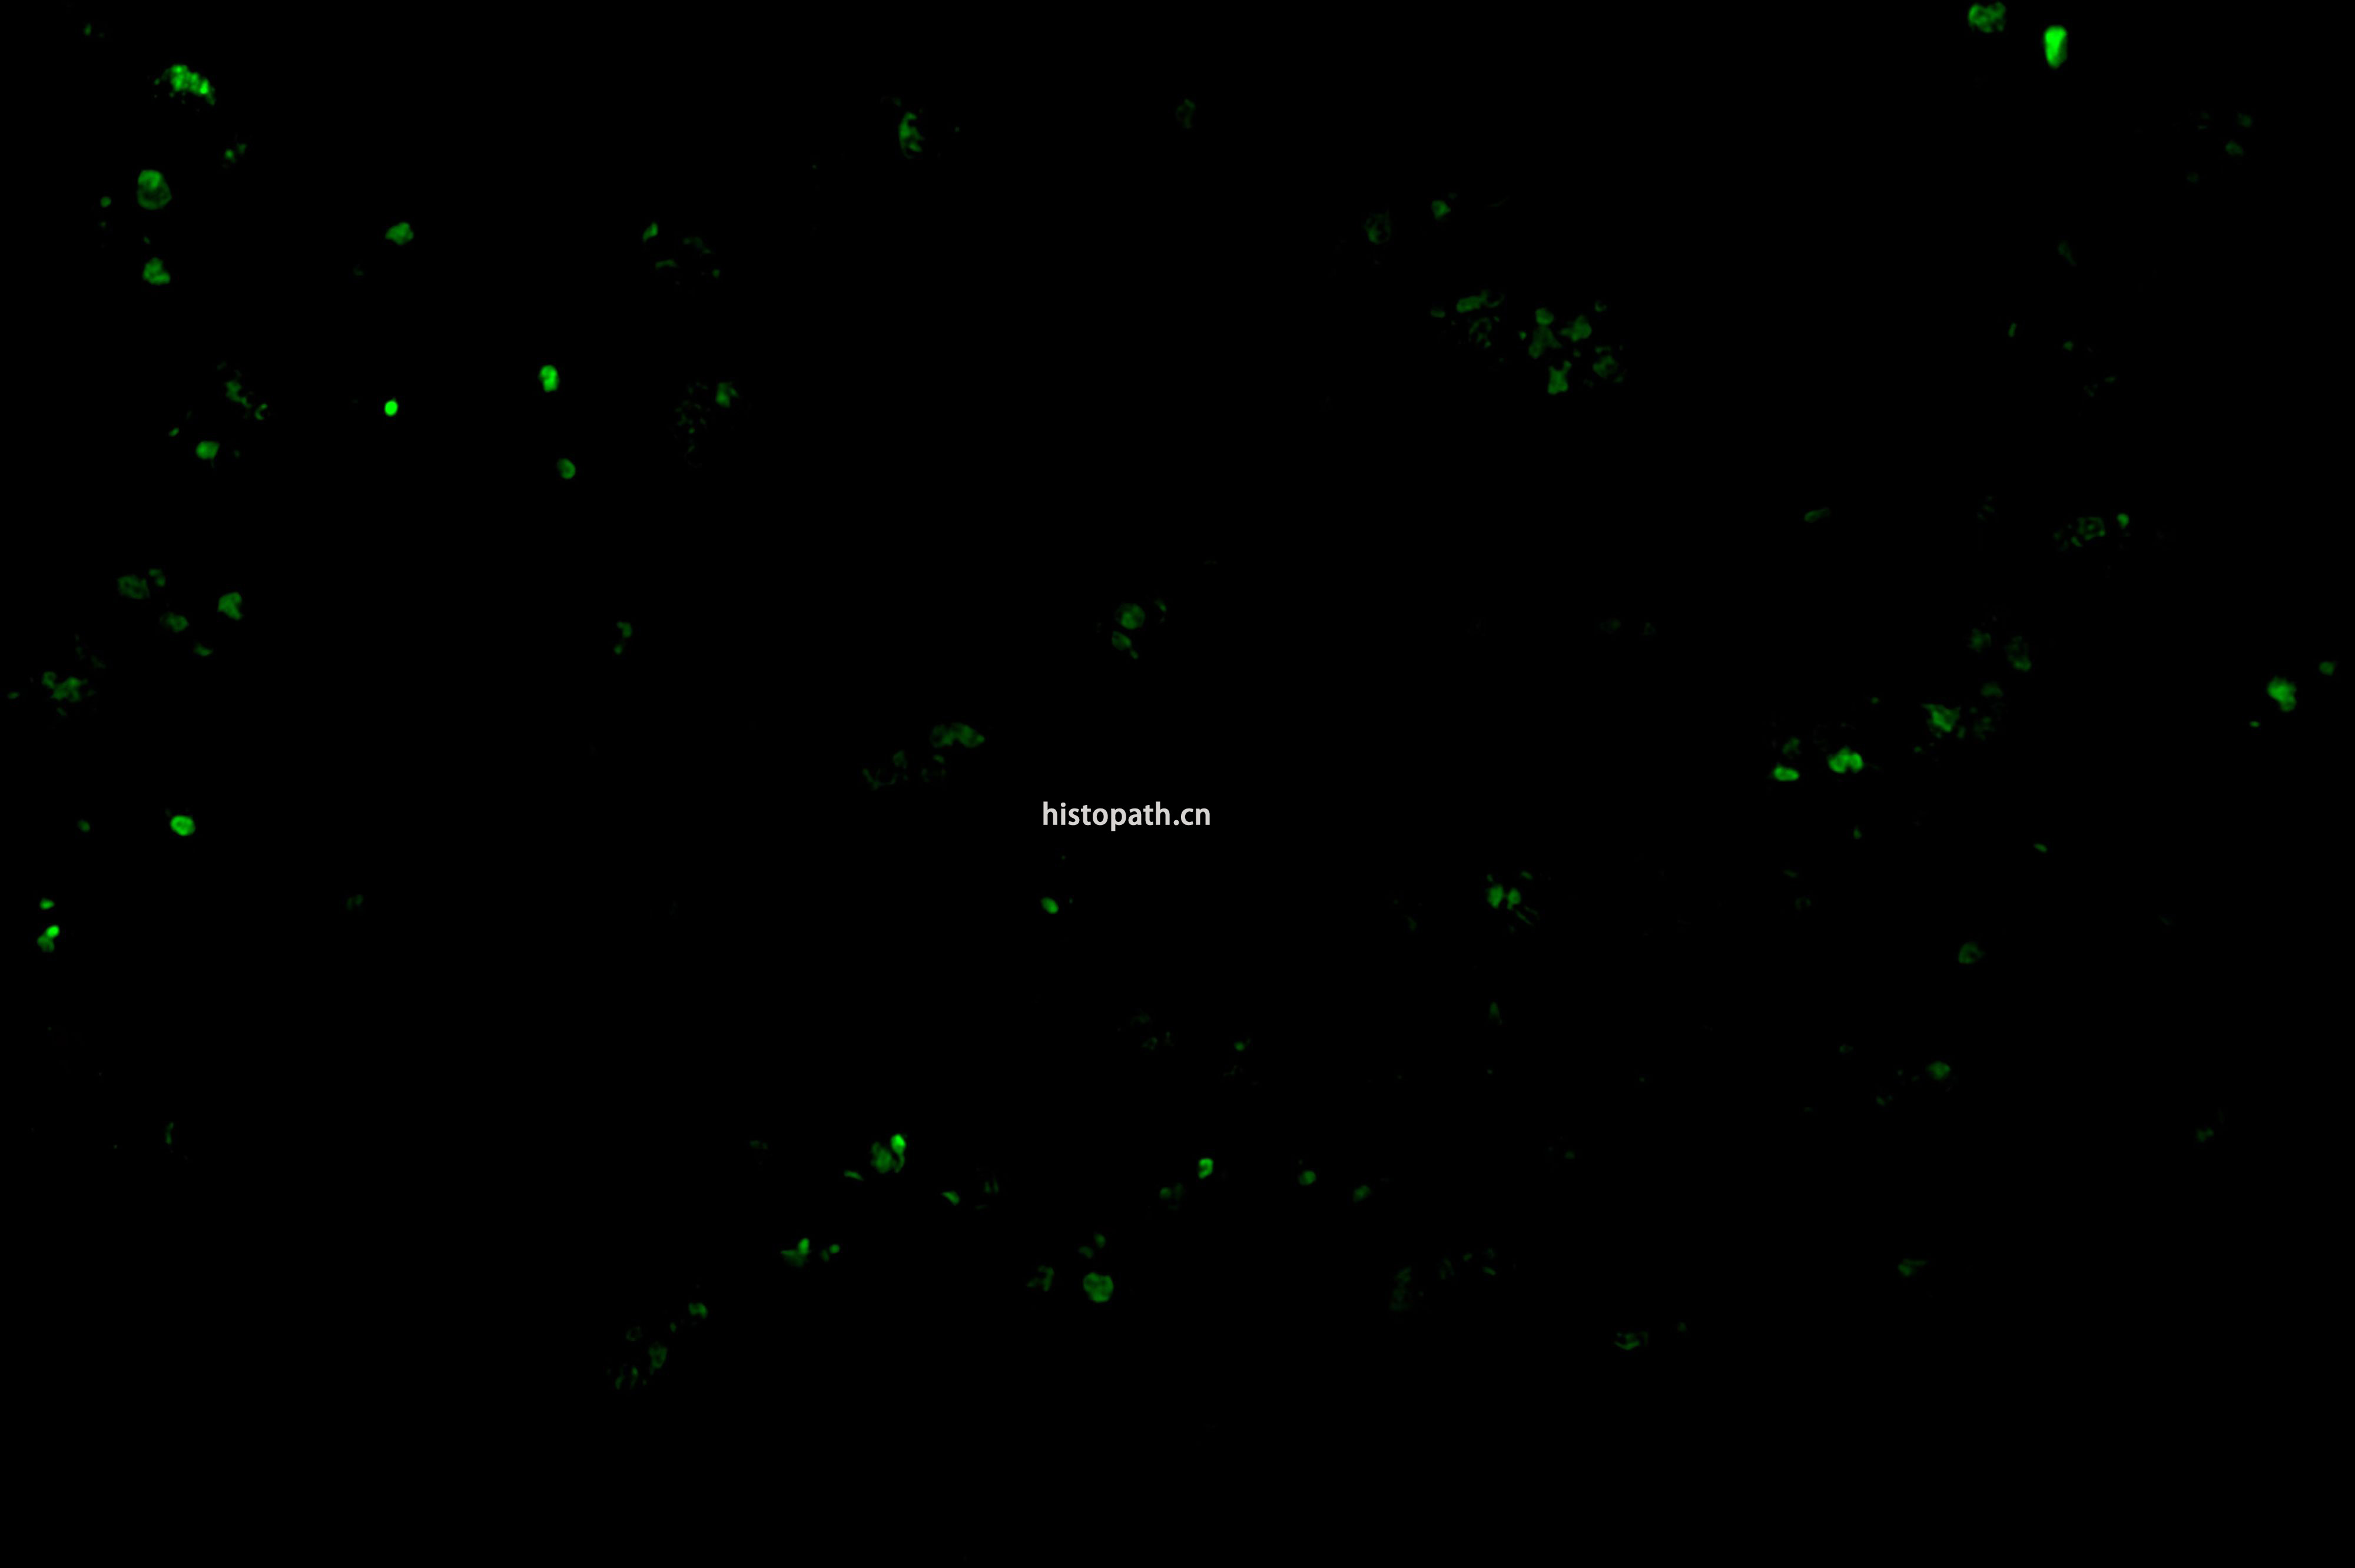

TUNEL染色荧光法

TUNEL检测原理:

细胞在发生凋亡时,会激活一些DNA内切酶,这些内切酶会切断核小体间的基因组DNA。细胞凋亡时抽提DNA进行电泳检测,可以发现180-200bp的DNA  ladder。基因组DN A断裂时,暴露的3'-OH可以在末端脱氧核苷酸转移酶(Terminal Deoxynucleotidyl TransferaseTT)的催化下加上绿色荧光探针荧光素(FITC)标记的dUTP(fluorescein-dUTP),从而可以通过荧光显微镜或流式细胞仪进行检测,这就是TUNEL(T dT-mediated dUTP Nick-End Labeling)法检测细胞凋亡的原理。